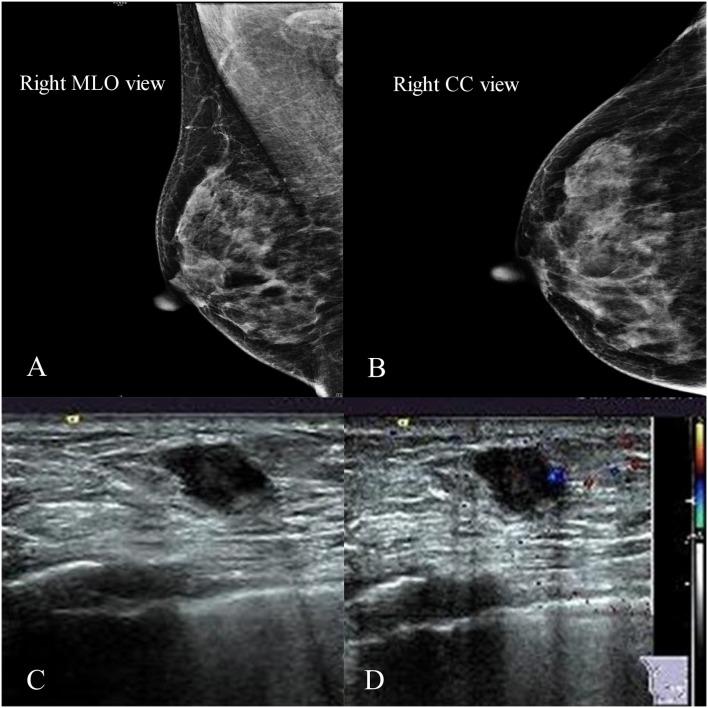

Metaplastic squamous cell carcinoma (SCC) of the breast is a rare and heterogeneous group of primary breast malignancies. The etiology, pathogenesis, and proper treatment for this kind rare breast cancer are still unclear. We reported a case of a 55-year-old woman with a palpable lump in the inner quadrant of the right breast. She underwent a right breast mass resection and sentinel lymph node biopsy, which revealed that the tumor was an invasive ductal carcinoma, followed by four cycles of doxorubicin plus cyclophosphamide and four cycles of docetaxel as adjuvant chemotherapy, and then simultaneous integrated boost intensity modulated radiotherapy to the whole right breast. After 2 years' follow-up, she had biopsy-proven disease recurrence in the right breast, which revealed SCC, and a mammogram showed abnormalities in the lower inner quadrant of the right breast and left axillary lymph nodes. Then we performed bilateral breast modified radical mastectomy, which confirmed that the recurrent tumors were metaplastic SCC, followed by adjuvant chemotherapy and adjuvant radiotherapy of the left supraclavicular and apical axillary regions. There has been no recurrent or metastatic evidence in the 16 months' follow-up since the second surgery. This case report shows that evolution of pathology type in recurrent breast cancer after initial treatment is possible. Detailed pathologic and immunohistochemical analyses are needed for identification of this change. Surgery and adjuvant radiation and chemotherapy are appropriate treatments for recurrent primary SCC of the breast.

乳腺化生性鳞状细胞癌(SCC)是一组罕见且异质性的原发性乳腺恶性肿瘤。这种罕见乳腺癌的病因、发病机制及恰当治疗仍不明确。我们报告了一例55岁女性,其右乳内象限可触及肿块。她接受了右乳肿块切除术及前哨淋巴结活检,结果显示肿瘤为浸润性导管癌,随后接受了四个周期的阿霉素加环磷酰胺及四个周期的多西他赛辅助化疗,然后对整个右乳进行同步整合加量调强放疗。随访2年后,她经活检证实右乳疾病复发,病理显示为SCC,乳房X线摄影显示右乳内下象限及左腋窝淋巴结异常。随后我们进行了双侧乳腺改良根治术,证实复发性肿瘤为化生性SCC,之后对左锁骨上及腋窝尖区进行了辅助化疗及辅助放疗。自第二次手术以来的16个月随访中,未发现复发或转移证据。本病例报告表明,初始治疗后复发性乳腺癌的病理类型可能发生演变。需要进行详细的病理及免疫组化分析以识别这种变化。手术及辅助放化疗是复发性原发性乳腺SCC的合适治疗方法。